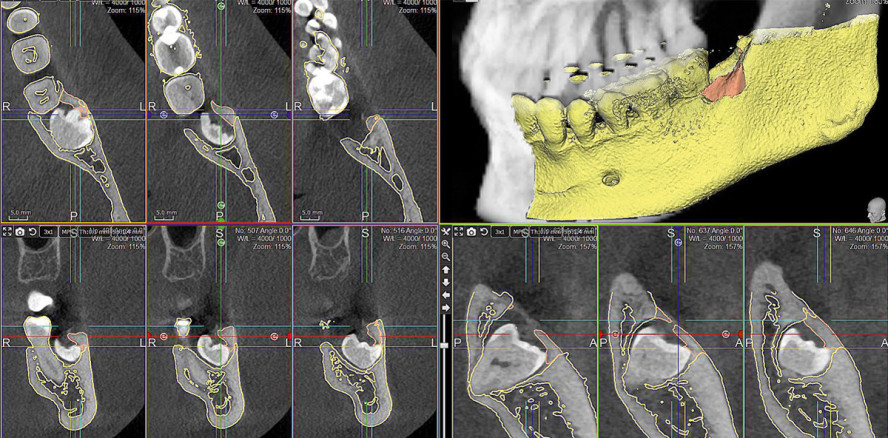

Die tiefe Impaktion und enge Nervbeziehung, welche sich in der Panoramaschichtaufnahme zeigte (Abb. 1), rechtfertigte die Anfertigung einer digitalen Volumentomografie (WhiteFox, ACTEON). Hier wurde zunächst der Verlauf des NAI analysiert und per grafischer Kennzeichnung markiert (Abb. 2a und b). Anschließend wurde der tiefste Punkt der Furkation anhand einer definierten Analyse der drei Schichten des DVT ausgewertet und festgelegt. In diesen Punkt wurde virtuell ein definierter Bohrstollen mit bukkaler und okklusaler Ausrichtung geplant. Dabei wurde ein Sicherheitsabstand von 2 mm zu Nachbarzahn, NAI und lingualer Kompakta eingehalten, wobei der bukkale Anstellwinkel zwischen 20° und 25°, der Winkel zur Okklusionsebene zwischen 40° und 50° liegen sollte (Abb. 3).

Mittels postoperativ angefertigten DVTs ließ sich der Knochenverlust unmittelbar grafisch darstellen. Dazu wurden die DICOM-Daten der Knochenoberfläche des linken Unterkiefers mittels 3Diagnosys® Software in eine STL-Oberflächengeometrie umgewandelt, welche anschließend per Best-Fit-Modus in die präoperative Aufnahme überlagert wurde. Anschließend wurden prä- und postoperative Knochenoberflächen exportiert. In der Freiformsoftware PlastyCAD wurden nun die Oberflächen voneinander subtrahiert, sodass der volumetrische Knochenverlust in allen Ebenen dargestellt werden konnte. Diese neu generierte „Knochenverlustoberfläche“ wurde zur exakten Messung in die präoperative DVT-Aufnahme eingeladen (Abb. 9–12).